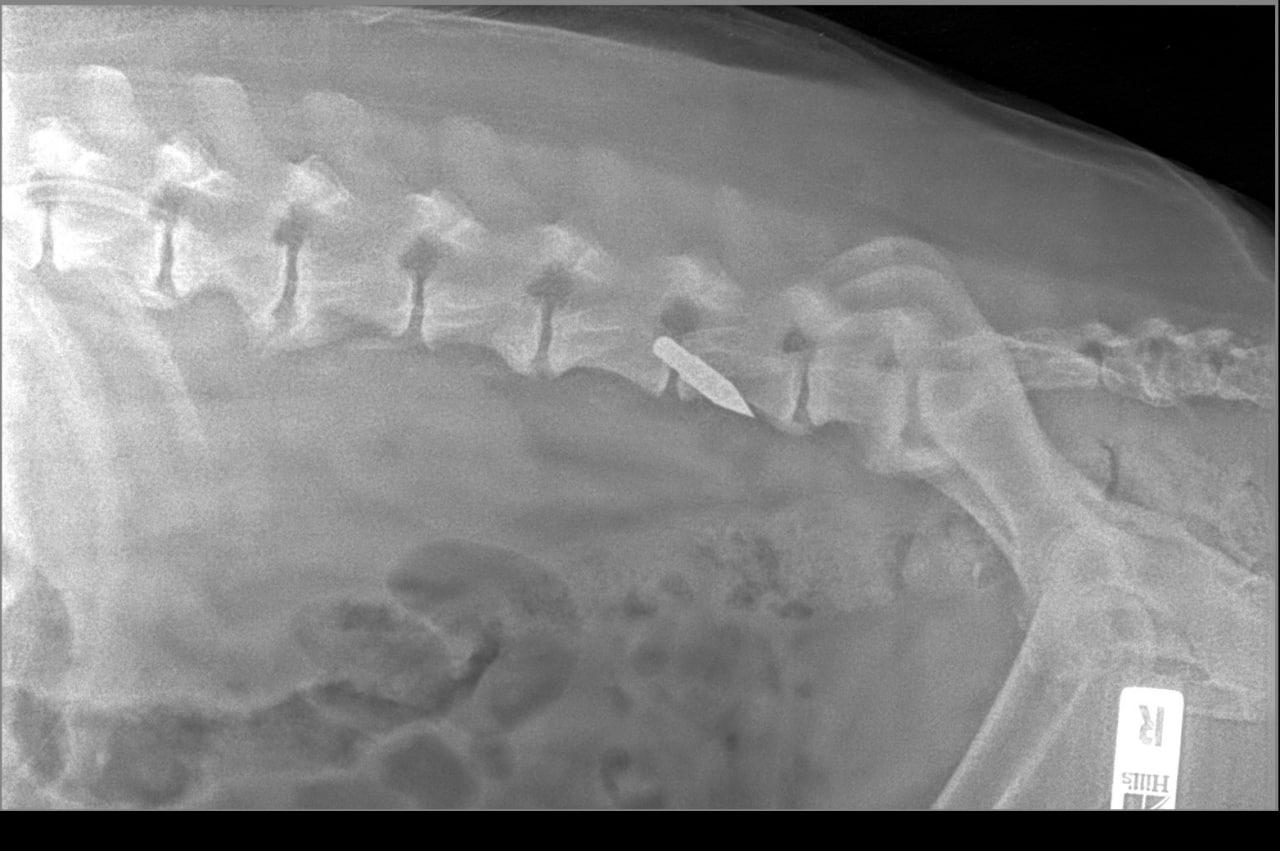

На теле собаки видны многочисленные раны от стрел арбалета.

По информации зоозащитников, пострадавший — кобель в возрасте 8–10 лет. Его обнаружили 22 февраля на улице Мелиораторов, 48а в районе ММС. Собака получила множественные ранения от стрел арбалета.